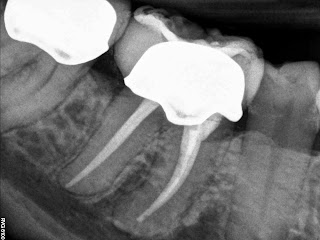

1 mesial canal, although it was ribbon shaped at pulpal floor.

| Angled can kind or see where ribbon portion canal is |